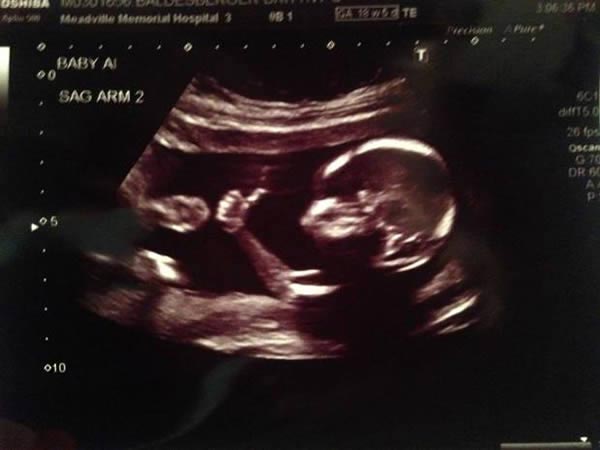

பின் 15வது வாரம் வரையில் ஒரு விதை வடிவ மூட்டை போன்ற குழந்தையையே காண முடியும். ஆனால், 27 முதல் 28 ஆம் வாரத்தில் குழந்தையின் முழு வளர்ச்சியை அதாவது முழுமையான உருவாக்கம் பெற்ற குழந்தையை மிகவும் தெளிவாக தாயின் வயிற்றில் காண முடியும். இந்த கண் கொள்ளா காட்சியை காட்ட கர்ப்ப கால ஸ்கேன் பரிசோதனை மிகவும் உதவுகிறது.

குழந்தை தாயின் கர்ப்ப காலத்தில் உருவான பின் முதன் முதலாக ஸ்கேன் பரிசோதனை மூலம் குழந்தையின் இருப்பிடத்தை மட்டுமே காண முடியும். பின்னர் ஒரு சில வாரங்களுக்கு பின் குழந்தையின் இதய துடிப்பை கேட்டு அறிய முடியும். இதன் பிறகு குழந்தைகளின் தலை மற்றும் தலையின் அமைப்புகள், உடலின் வடிவம் மற்றும் குழந்தை உள்ள அம்னியாட்டிக் சாக் போன்ற உறைகள் இவற்றையும் ஸ்கேன் பரிசோதனை மூலம் காண முடியும்.

குழந்தைகள் தாயின் வயிற்றில் வளரும் பொழுது எடுக்கப்படும் ஸ்கேன் பரிசோதனைகளில் பல விதங்கள், பல வகைகள் உள்ளன. இந்த ஸ்கேன் பரிசோதனைகளின் வகைகளை இப்பொழுது பார்க்கலாம்: ஸ்டாண்டர்ட் ஸ்கேன் பரிசோதனை என்பது 2D வடிவில் கருவறையில் உள்ள குழந்தையை காட்டுவதற்கு உதவும்.

டாப்ளர் இமேஜிங் ஸ்கேன் பரிசோதனை மூலம் குழந்தையின் உடலில் உள்ள இரத்த ஓட்டம் போன்ற விஷயங்கள் குறித்த தகவல்களை பற்றி அறியலாம்.

ஸ்கேன் பரிசோதனைகளில் மேலும் இரண்டு வகைகள் உள்ளன; அவை என்னென்ன என்றால், ட்ரான்ஸ்வெஜினல் அல்ட்ராசவுண்ட் ஸ்கேன் பரிசோதனை மூலம் குழந்தை உருவாக்கத்தின் நிலைகளை தெளிவாக, சிறந்த தரத்தில் படங்களாக பார்த்து அறிய முடியும். மேலும் ஃபெடல் எக்கோ கார்டியோகிராபி ஸ்கேன் பரிசோதனை மூலம் குழந்தைகளின் இதயம் தொடர்பான அனைத்து விஷயங்களையும் பற்றி அறிந்து கொள்ளலாம்.